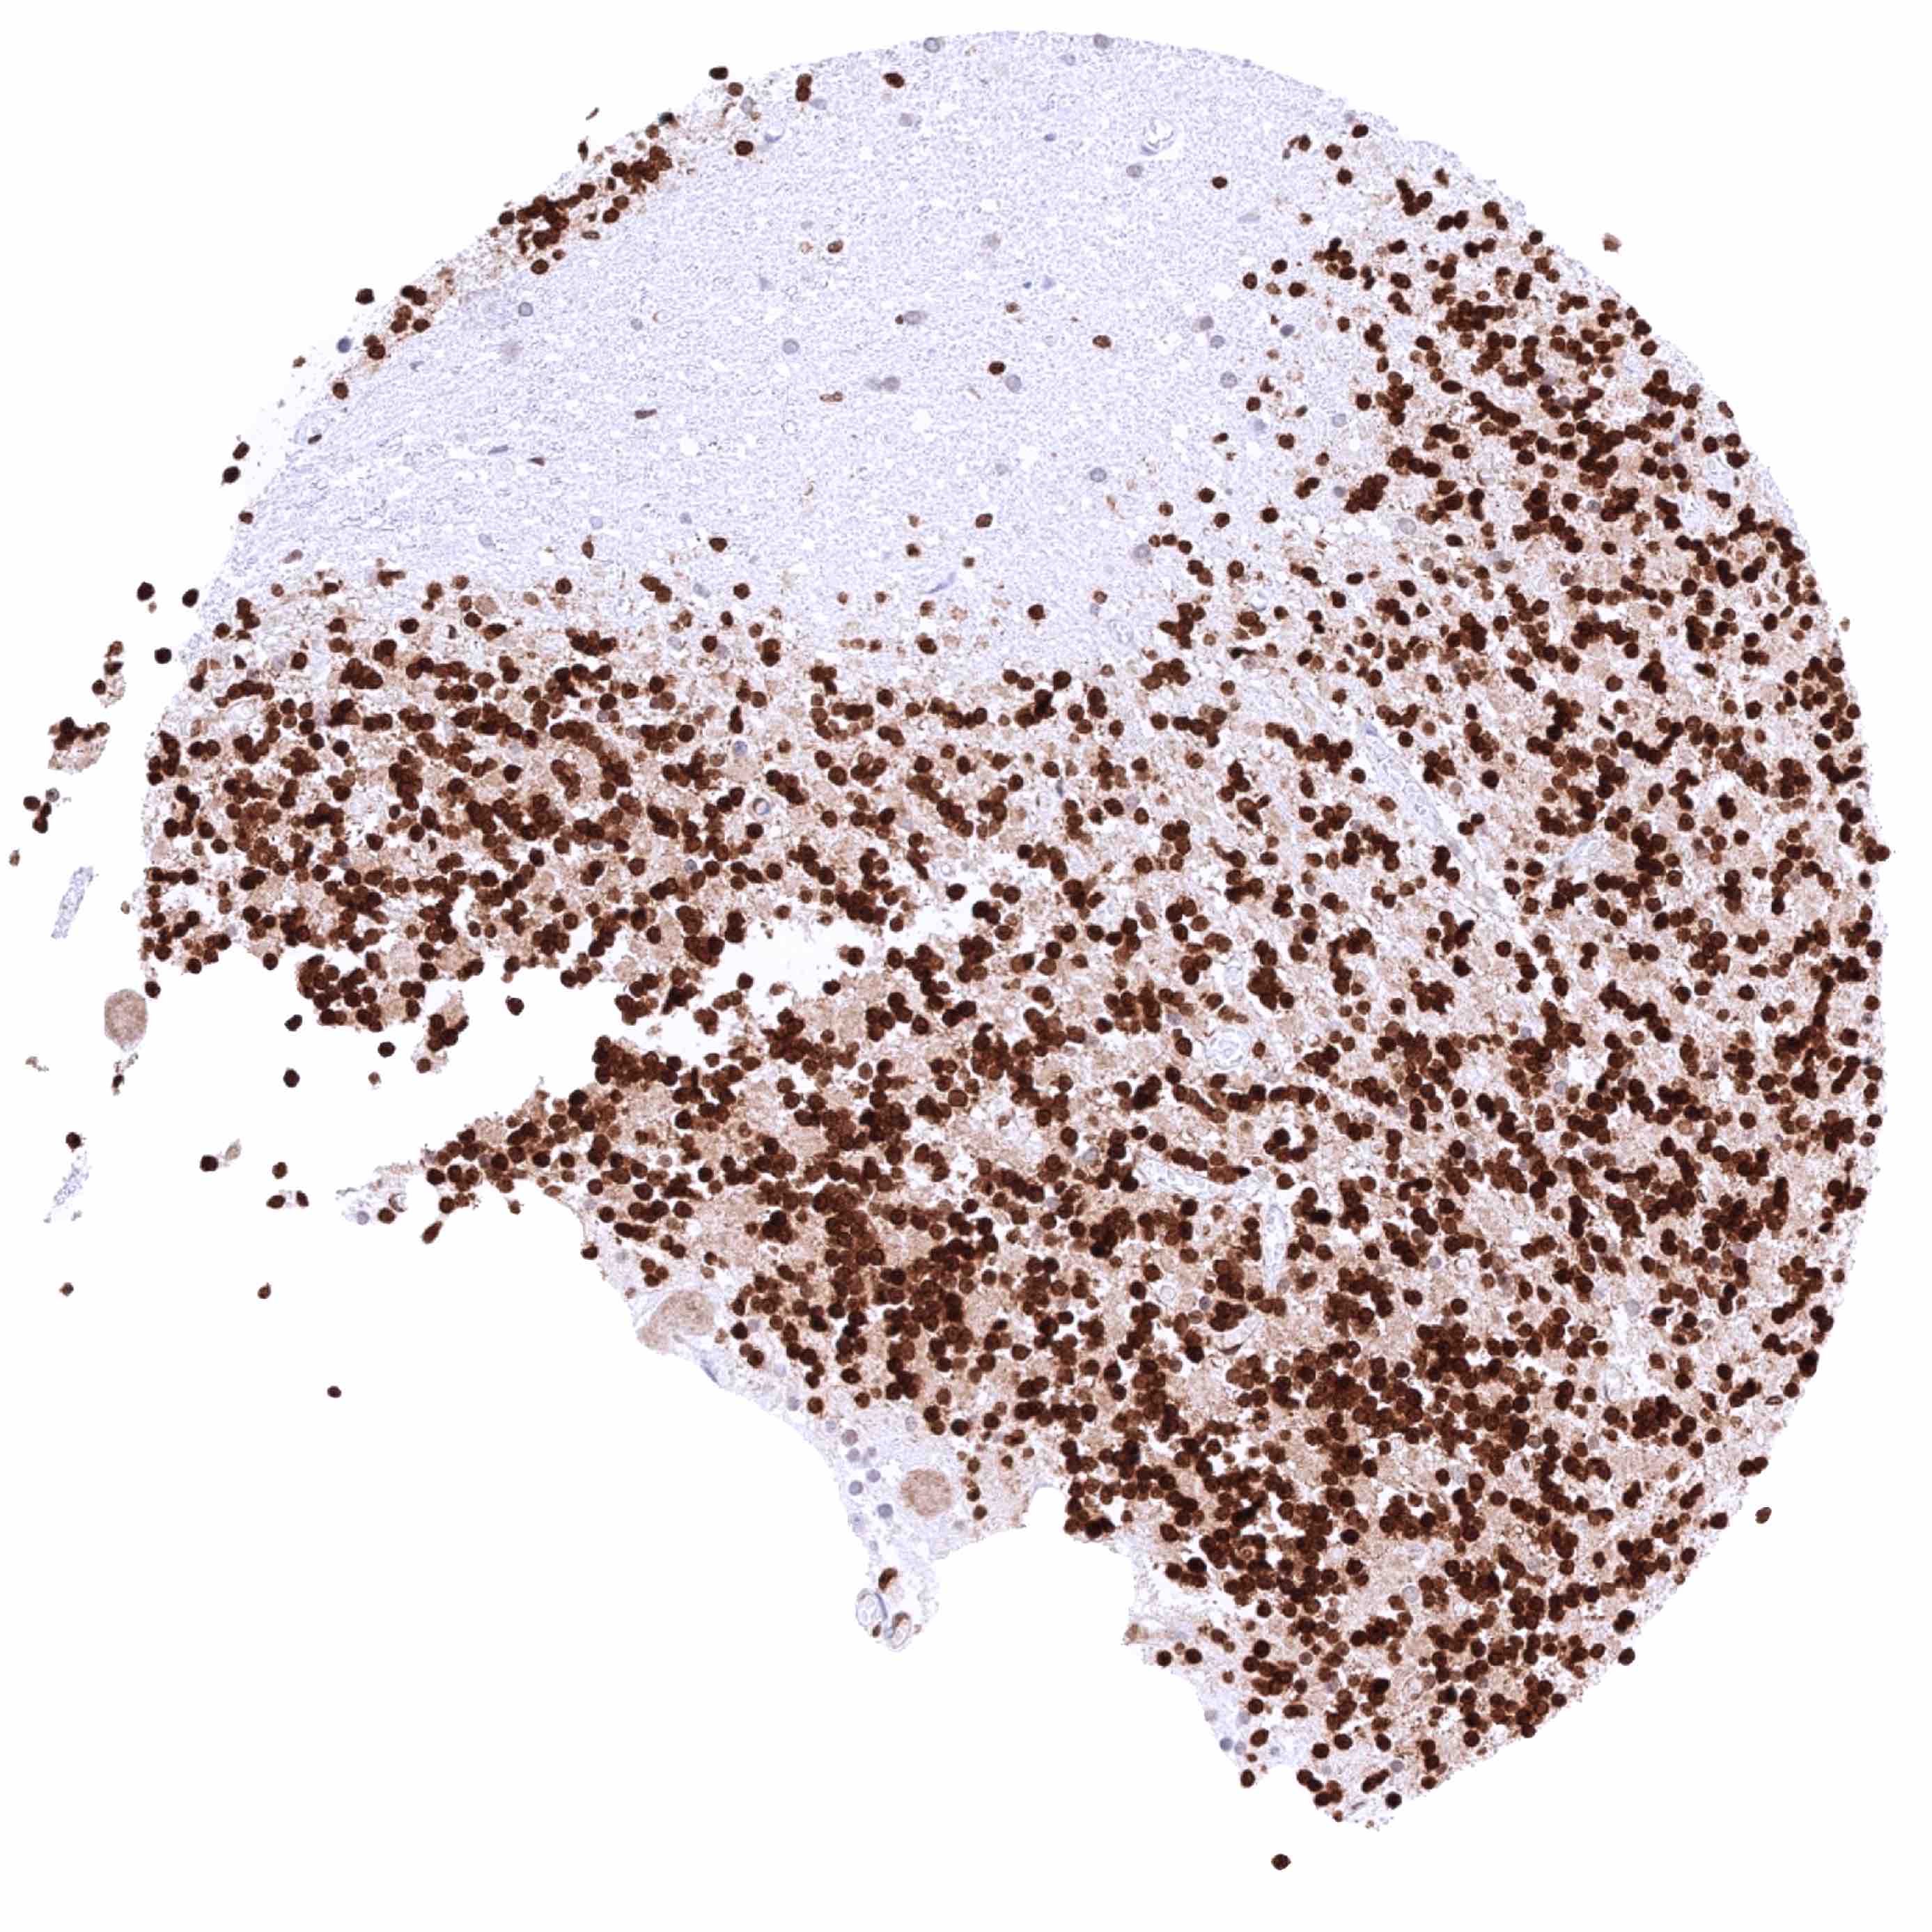

Bone marrow – Intense nuclear HMGB1 staining of virtually all cells of the hematopesis